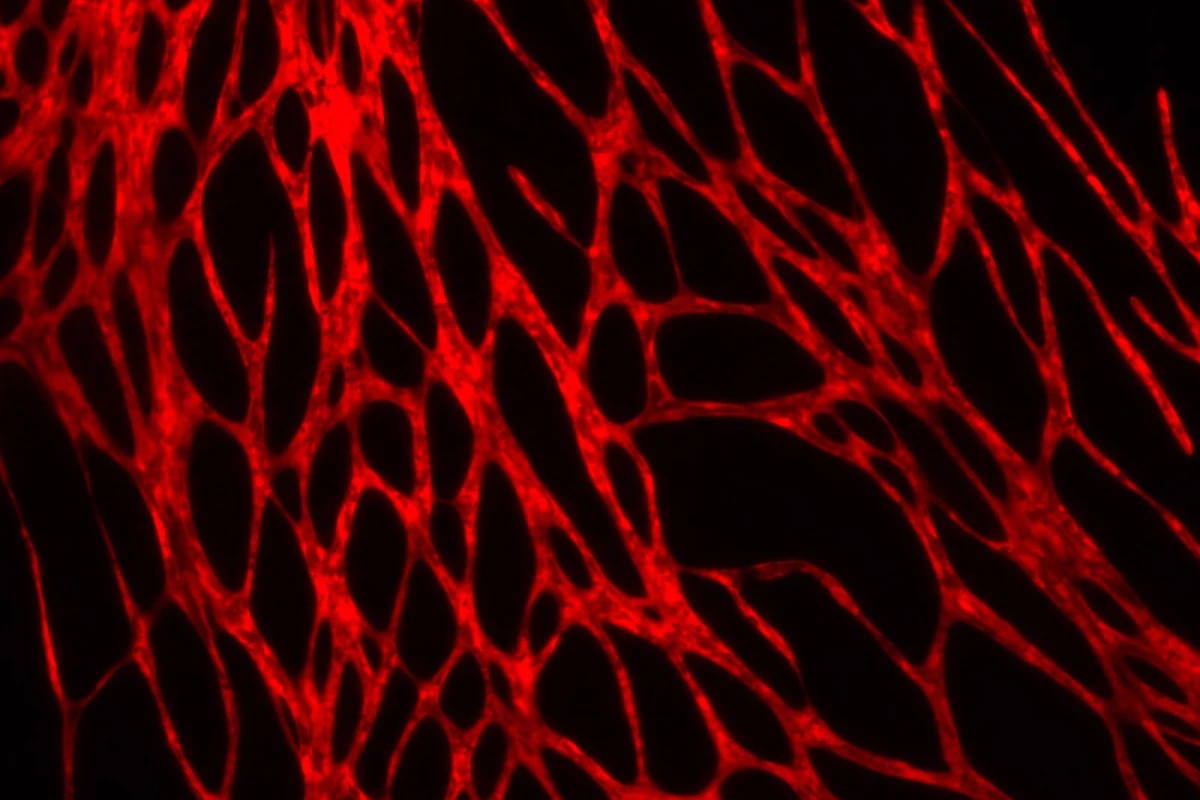

Within the space of a few weeks, blood vessels began growing in skin that had been printed from the new bio-inks. When these pieces of the skin were grafted over open wounds on mice, the animals' blood vessels began communicating with those in the bioprinted skin, causing the grafts to become perfused with blood after four weeks.